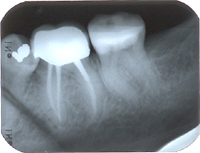

In Abb. 2 ist das Röntgenbild 22 Jahre nach korrekter Wurzelbehandlung mit dem nun überkronten Zahn zu sehen. Der Knochen um die Wurzelspitzen ist entzündungsfrei gesund.